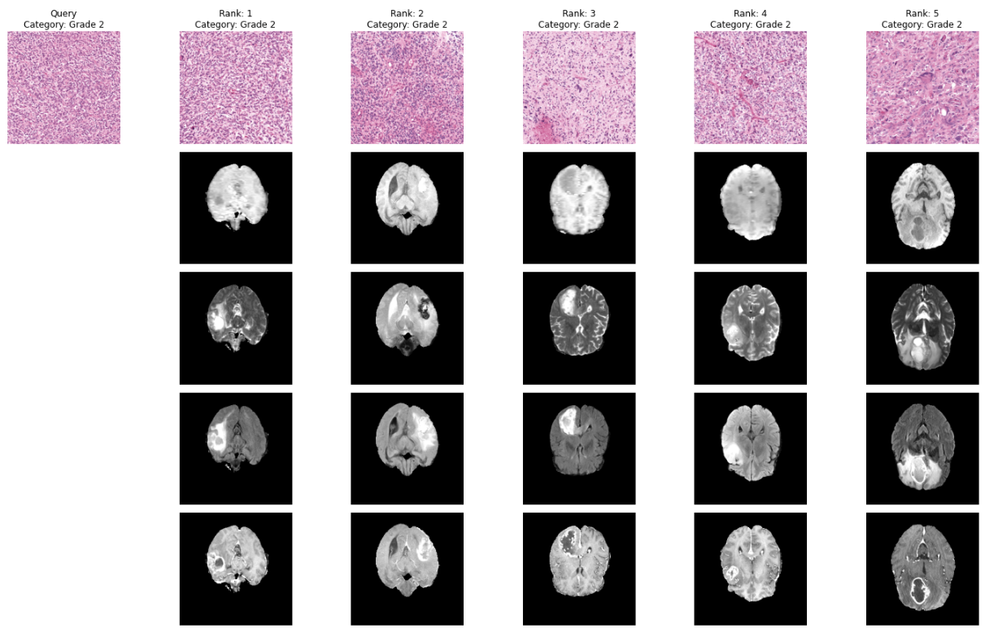

Once we can reliably generate embeddings, the rest of the search engine is straightforward: we compute embeddings for the pathology corpus, build a FAISS index (e.g., flat L2 for a baseline), and then run query → embedding → nearest neighbors to retrieve similar pathology cases. Example retrieval results across tumor grades (0–2) are shown in Figure 2. To make “similarity” more clinically meaningful, we optionally apply a lightweight adapter implemented as a small MLP, on top of the foundation embeddings. In the notebook, the adapter takes 1536-D GigaPath embeddings as input (in_channels=1536) and produces a compact 254-D representation (adapter_emb_size=254), trained with a simple 3-class objective (num_class=3, Grades 0/1/2). This is intentionally lightweight compared with retraining the foundation model: we only learn a small mapping from embeddings to a better-aligned space, then rebuild the FAISS index using the adapted vectors (gigapath_adapter_features) to improve retrieval relevance. The effect of this optimization is visualized in Figure 3, which contrasts the baseline embedding space with the adapter-optimized space.

Figure 2. Nearest-neighbor retrieval examples for Grade 0, Grade 1, and Grade 2 queries.

Collectively, these results indicate that the refined embedding space makes similarity more grade-consistent, which is exactly what diagnostic concordance workflows need: when clinicians retrieve “similar” pathology cases, they want those neighbors to reflect clinically relevant groupings (here, tumor grade), and to remain interpretable when linked to the corresponding radiology context. The fact that Grade 1 benefits most is also plausible from a pathology standpoint: intermediate grades often show more overlap in morphology with both lower and higher grades (i.e., less separable visual patterns), while higher grades may exhibit more distinctive features that are easier to retrieve correctly even without refinement. In that sense, the lightweight adapter acts as a targeted calibration step: shaping the embedding space so that ambiguous, overlapping cases (like Grade 1) are pulled closer to the right neighbors.

Figure 4. Histopathology (H&E) retrieval with linked radiology (MRI) context.